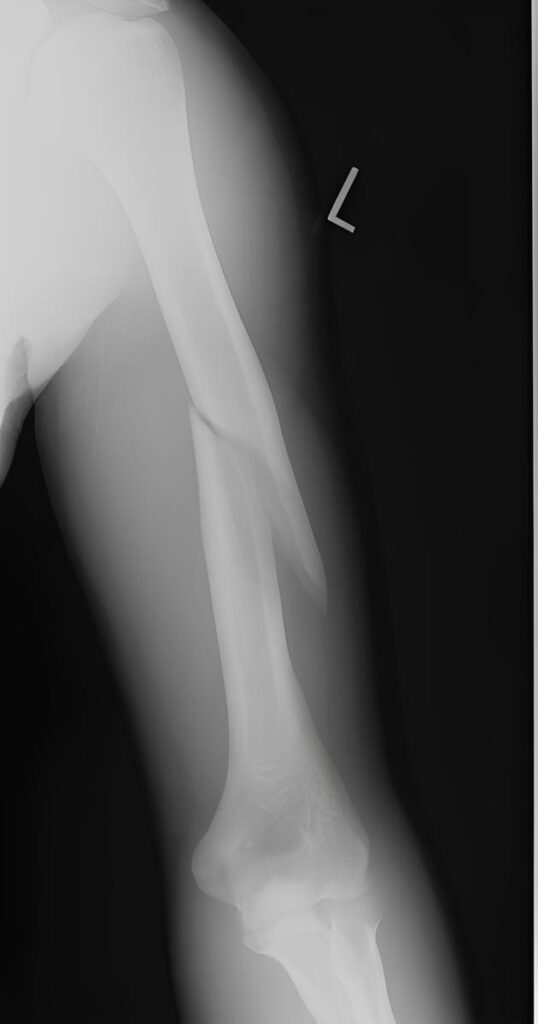

Definition Galeazzi Fracture is defined as a fracture of the distal or middle third of the radius accompanied by dislocation or subluxation of the distal radioulnar joint. It is often referred to as a “fracture of necessity” because surgical management is usually required in adults. Mechanism of Injury In children, the injury may occur with …